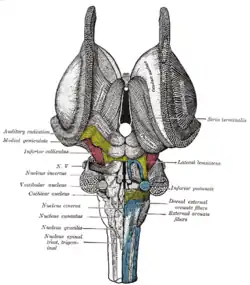

Superficial dissection of brain-stem. Ventral view. Dissection of brain-stem. Dorsal view.

Dissection of brain-stem. Dorsal view. Central part and anterior and posterior cornua of lateral ventricles exposed from above.